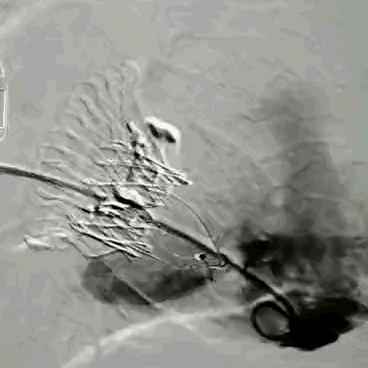

LuX-Valve®经导管三尖瓣置换系统